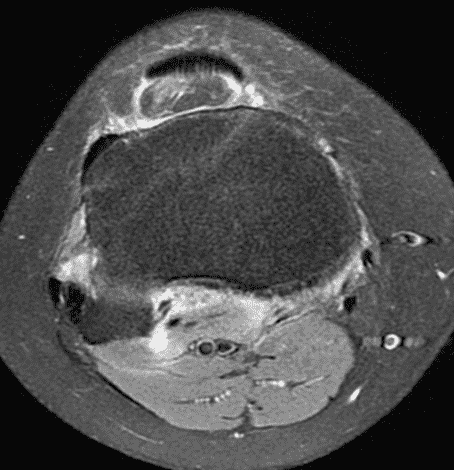

A 19 year-old woman complains of 9 months of unilateral right knee pain and persistent knee swelling without known injury or systemic symptoms. Coronal (1A), sagittal (1B), and transverse (1C) fat-suppressed T2-weighted images of the right knee are provided. What are the findings? What is your differential diagnosis?

Figure 2: (2A) The coronal image shows a large effusion and severe hypertrophic synovitis (asterisks) in the knee. (2B) On the sagittal image the hypertrophic synovium (asterisks) involves the suprapatellar and infrapatellar recesses as well as the anterior and posterior intercondylar notch. A reactive lymph node (arrow) is present in the popliteal fossa. (2C) The axial image demonstrates myositis (arrows) involving the popliteus and peroneus longus muscles. Note the preserved articular cartilage, lack of erosions, and the absence of subcutaneous or marrow edema.